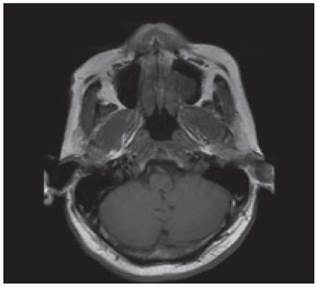

<p>Los estudios de hemograma, nitrógeno ureico, creatinina, glucemia y electrolitos se encontraron dentro de los rangos normales, el perfil lipídico mostró: colesterol total 160 mg/dl, colesterol HDL 50 mg/dl, colesterol LDL 89,8 mg/dl, triglicéridos 101 mg/dl. La tomografia de cráneo simple no mostró sangrado ni signos de isquemia. Se realizó una resonancia magnética cerebral simple que permitió evidenciar en las secuencias de T2 y FLAIR <italic>(Fluid Attenuation Inversion Recovery)</italic> una zona de hiperintensidad de señal a nivel del bulbo raquídeo en la región dorso-lateral caudal izquierda que es hipointensa en T1 (<xref ref-type="fig" rid="f1">figuras 1</xref>,<xref ref-type="fig" rid="f2">2</xref>,<xref ref-type="fig" rid="f3">3</xref>,<xref ref-type="fig" rid="f4">4</xref>). En la secuencia de difusión se observa restricción de la misma en la zona descrita con fenómeno de pseudonormalización al igual que en el mapa ADC <italic>(Apparent Coefficient Diffusion}</italic> (<xref ref-type="fig" rid="f5">figuras 5</xref>,<xref ref-type="fig" rid="f6">6</xref>). Los anteriores hallazgos se interpretaron como compatibles con un infarto bulbar lateral izquierdo.</p>

<p>El paciente se caracterizó por tener principalmente dis-fagia, disfonía, vértigo, ataxia y hemiparesia ipsilateral, las cuales rápidamente mejoraron, siendo llamativo la ausencia de nistagmo el cual se reporta en una incidencia importante. El estudio por resonancia magnética se logró realizar 1 semana posterior al inicio de los síntomas, lo cual generó la limitante de observar pseudo-normalización en la secuencia DWI (Diffusion Weighted Imaging) y por ende ausencia de una clara restricción de la difusión. En el T2 corte coronal se puede ver extensión hacia zonas caudales de la unión bul-bomedular, lo cual explicaría por qué presentó compromiso del tracto cortico-espinal siendo la primera causa, la lesión de las fibras ya decusadas provenientes del hemisferio contrala-teral ya sea por isquemia o por efecto de masa por el edema adyacente, este hallazgo se correlaciona con lo mayormente reportado en otras publicaciones. Un elemento importante en el paciente fue el inicio súbito de los síntomas posterior a realizar una rotación brusca del cuello con dolor cervical asociado, lo cual debe ubicar al clínico en un contexto cuya principal etiología a estudiar sea la disección cervical dada además la ausencia de factores de riesgo cardiovasculares y la edad cercana a los 50 años, sin embargo, en una angiografía convencional tomada 3 semanas después, no se evidenció esta etiología según lo informado por radiología. A pesar del compromiso motor, no todos los pacientes que cursan con síndrome de Opalski tienen una afectación marcada de la funcionalidad e independencia <xref ref-type="bibr" rid="B17"><sup>17</sup></xref> y la debilidad evidenciada es leve y transitoria permitiendo su recuperación hasta el 100 % previo, como se observó en este caso. Por otro lado, es importante evitar complicaciones tempranas como la broncoaspiración y neumonitis secundaria y, por ende, se hace imperativo plantear desde el ingreso de estos pacientes una vía alterna de alimentación a través de sonda naso u orogástrica o gastrostomía mientras se lleva a cabo el proceso de rehabilitación de la disfagia de forma paralela.</p>